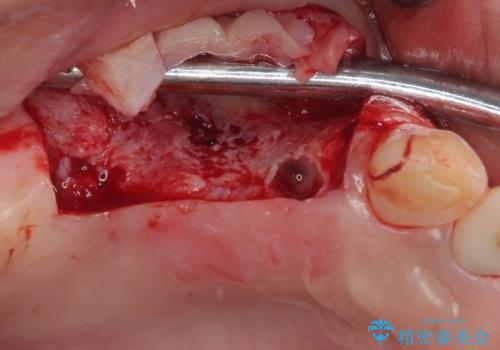

臼歯はもはや咬み合わせに寄与していない状態であり、3歯を抜去してインプラント2本埋入によるブリッジ補綴を計画しました。

臼歯部は前歯以上に炎症が酷く、抜歯即時埋入不可と判断されましたが、従来法よりは短期間で終えることができました。